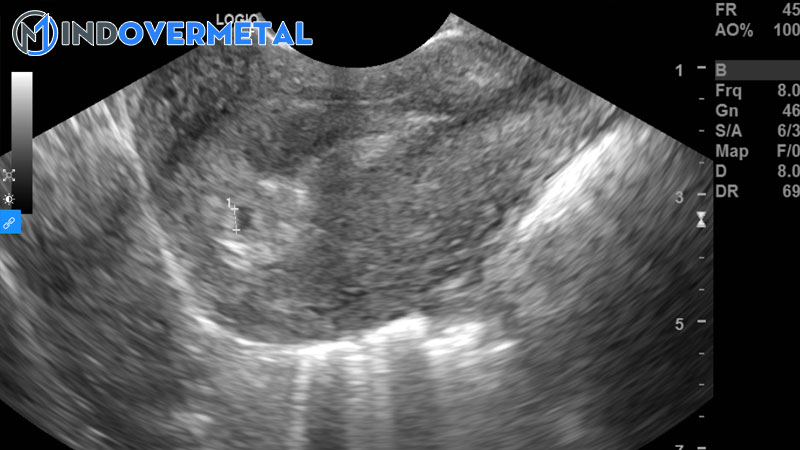

Việc siêu âm có túi thai nhưng chưa thấy phôi thai ở tuần thứ 5 là thông thường, bác sĩ sẽ khuyên mẹ nghỉ ngơi khoảng chừng 1-2 tuần rồi kiểm tra tiếp hoặc ngay khi có những bộc lộ không bình thường như ra huyết, đau bụng. Tùy từng hiệu quả siêu âm kiểm tra lại, nếu vẫn chưa có phôi thai, bác sĩ sẽ tìm nguyên do và cho mẹ giải pháp hài hòa và hợp lý nhất

Việc siêu âm có túi thai nhưng chưa thấy phôi thai ở tuần thứ 5 là thông thường ( Ảnh minh họa )